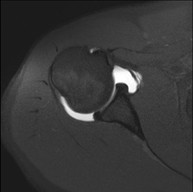

- RM d'Espatlla

Exploració per a l'estudi de lesions en els tendons, els músculs i les articulacions. La seva principal utilitat resideix en diagnosticar les lesions dels tendons del braçal rotatori. Té una durada aproximada de 20 minuts. No utilitza radiació ionitzant. - RM de Braç

Exploración para el estudio de las lesiones en pequeñas estructuras anatómicas de la articulación que suelen lesionarse en pacientes que sufren luxación o inestabilidad crónica. El estudio viene precedido por una inyección de contraste en el interior de la articulación, realizada bajo control de rayos X. La duración global de los dos procedimientos es de 50 minutos. - Artro-RM Muñeca